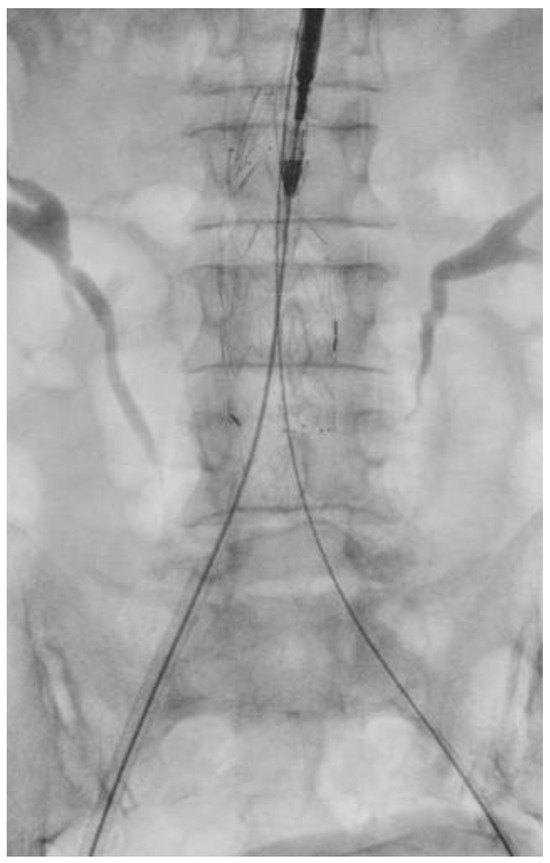

Surgical Technique